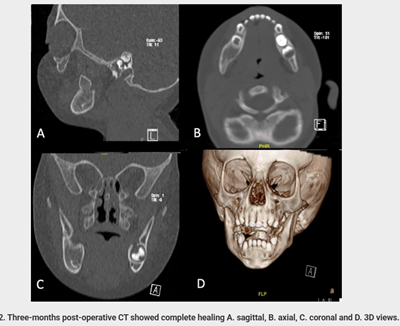

- Follow-up CT showed:

- Complete bone healing

- Absence of residual or recurrent pathology